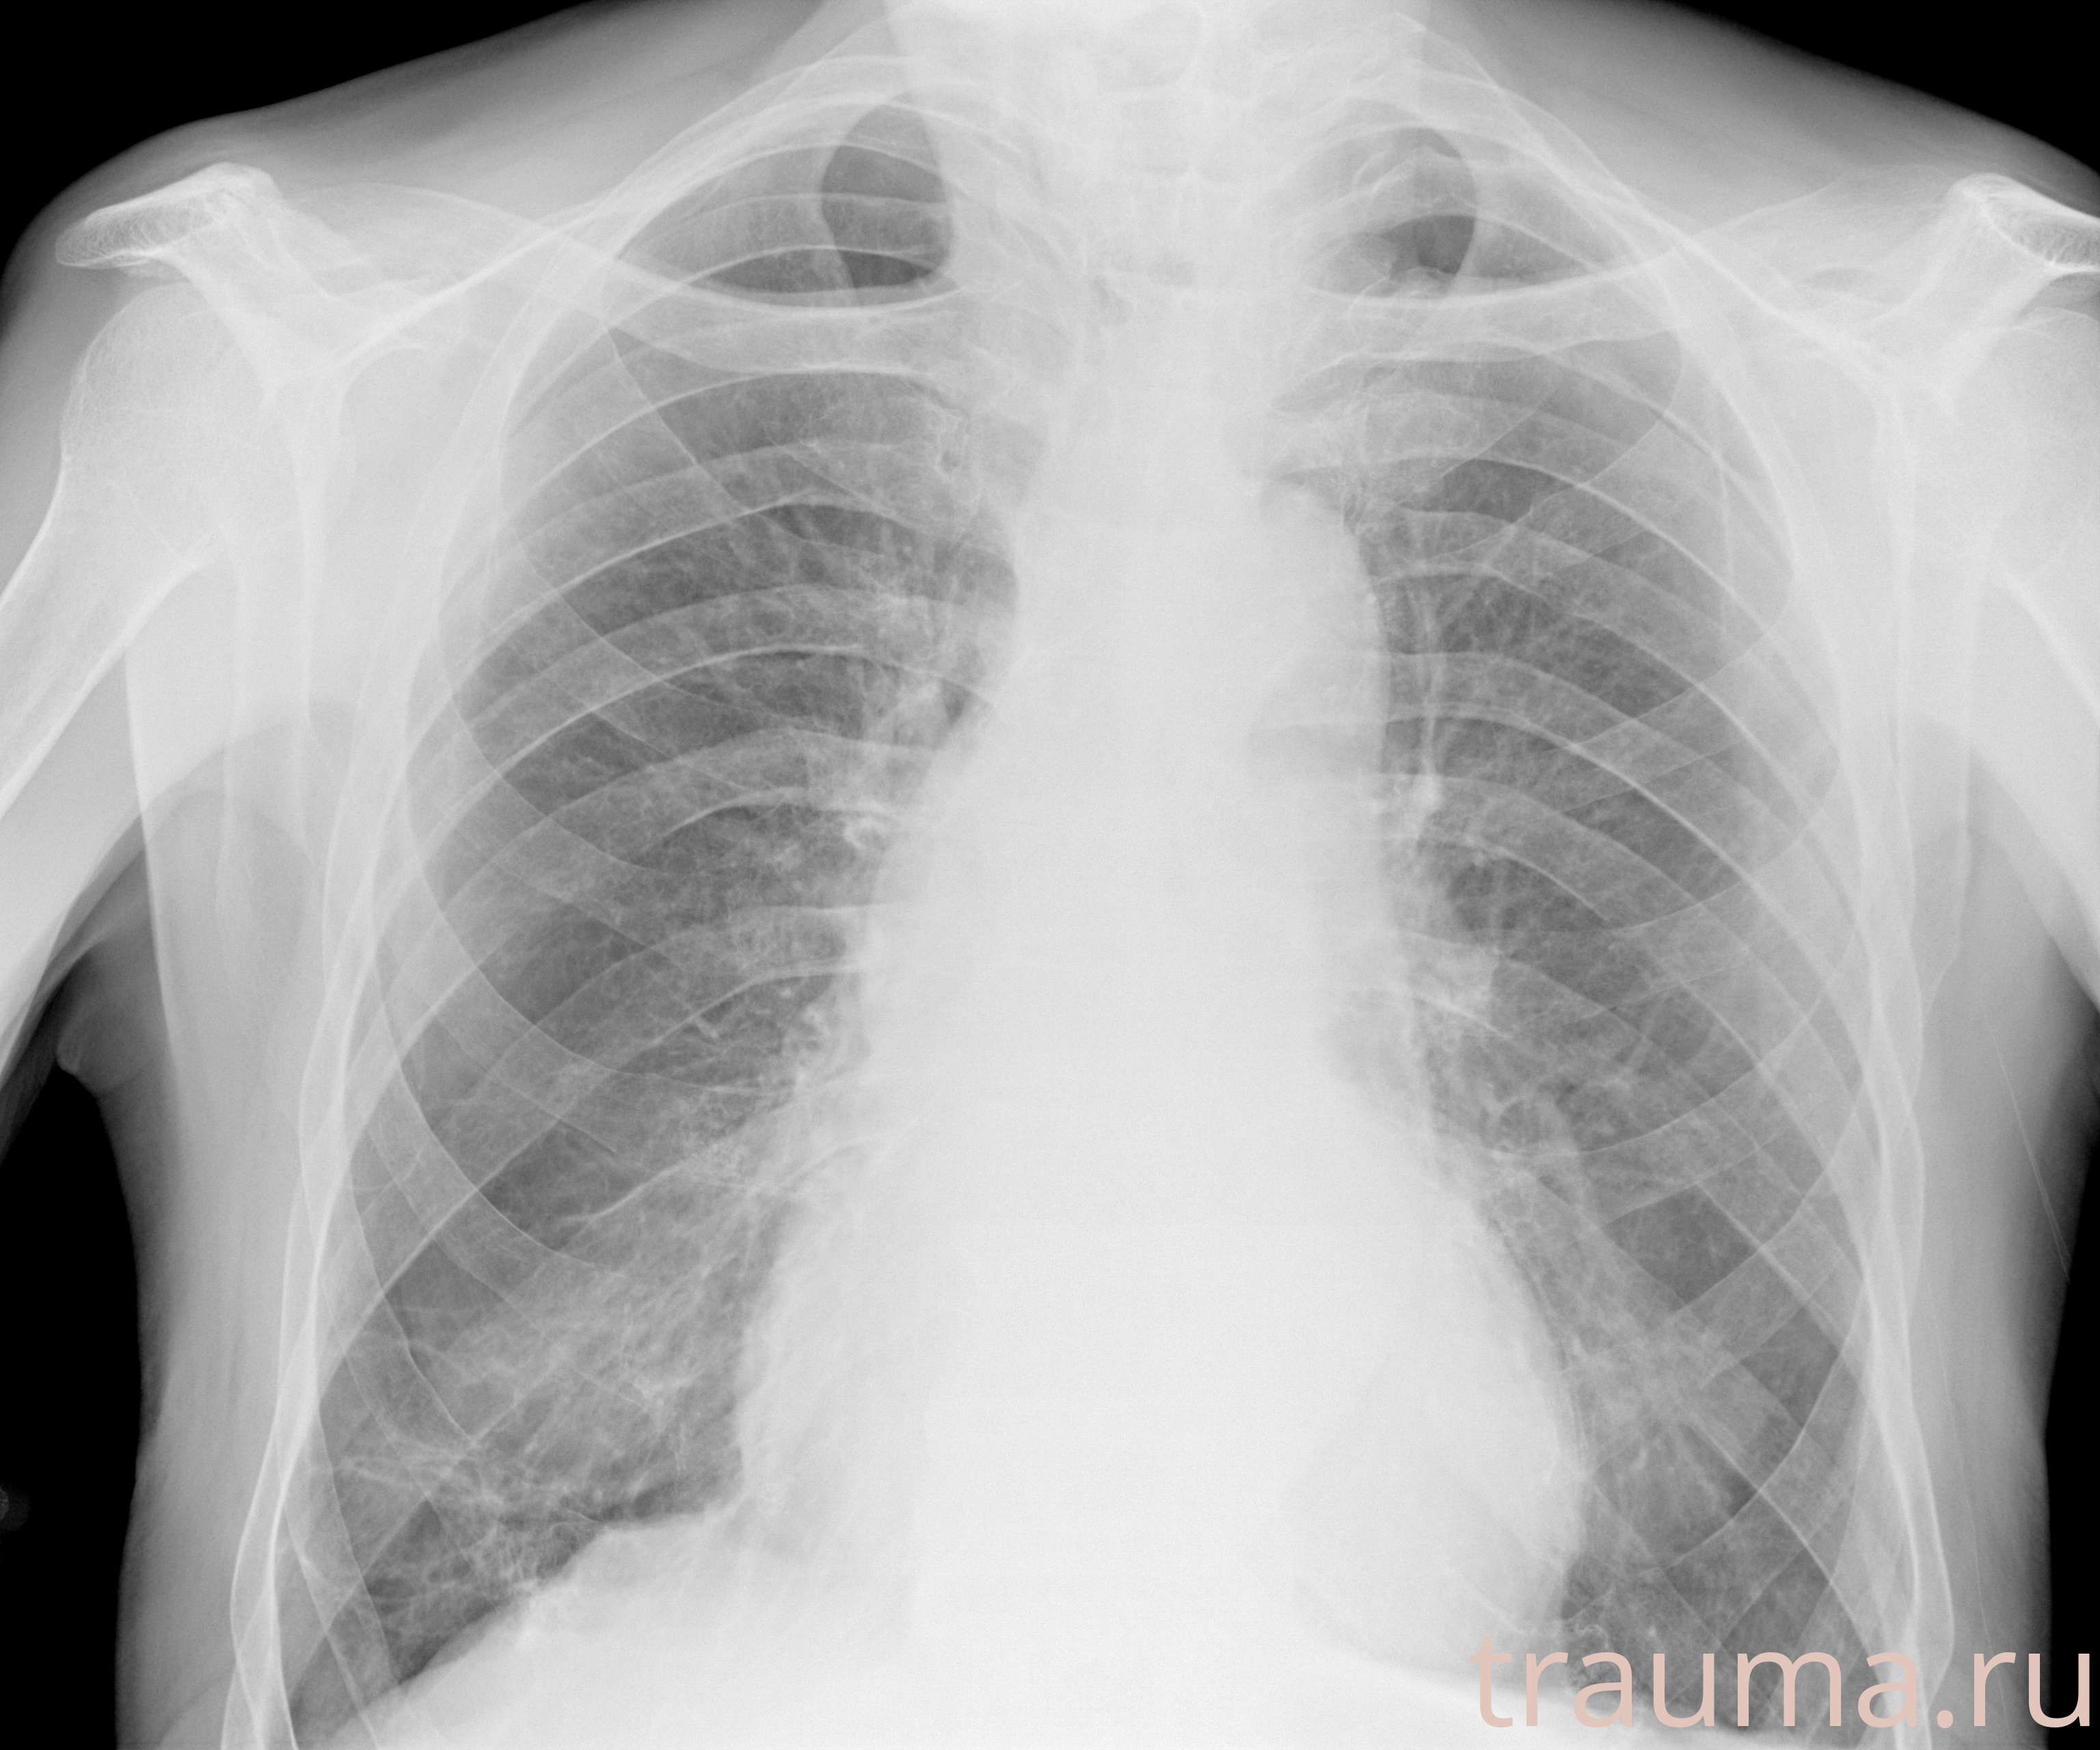

Рентгенограммы

Рентген на дому: по вашему адресу приезжает врач-рентгенолог, травматолог-ортопед с мобильным рентгеновским аппаратом, проводит диагностику травмы или заболевания, делает необходимые рентгенограммы, дает рекомендации по дальнейшему лечению. Получить качественные снимки в домашних условиях возможно благодаря уникальной методике, разработанной МосРентген Центром для института  Склифосовского

при переломе шейки бедра и пневмонии от компании МосРентген Центр - партнера Института имени Склифосовского